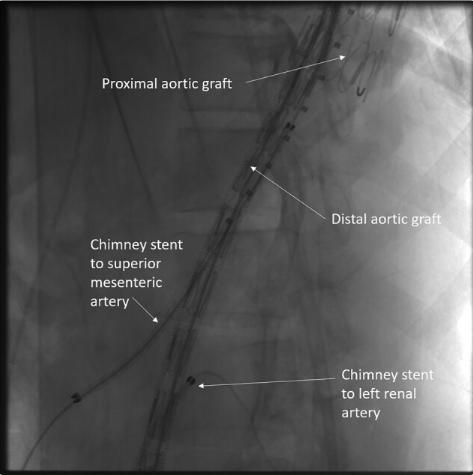

血管内修复:血管通路取自双侧股动脉和肱动脉。将34×30×200 mm的主动脉支架移植物(安库拉TAA支架移植物,深圳生命科技有限公司,中国)植入左锁骨下动脉远端。SMA支架采用8×100 mm和10×60mm覆膜支架。第二个尺寸为34×26×200 mm的主动脉支架移植物从远端胸主动脉放置到肾下主动脉。第一和第二主动脉移植物重叠6-7cm(图2)。SMA支架夹在两个移植物之间。通过左股动脉用6×80mm覆膜支架对左肾动脉进行支架植入。最终的血管造影没有发现内漏。腹腔动脉没有支架,因为它是从SMA逆行供血。

图2、血管内动脉瘤修复术